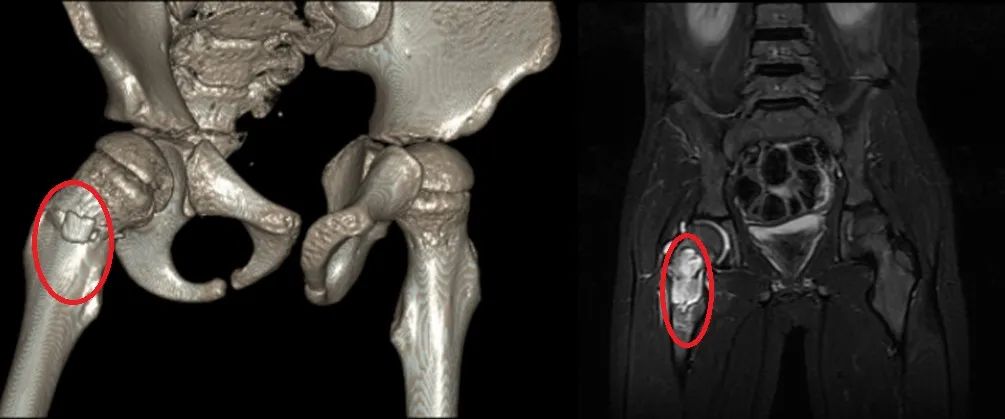

接诊医生仔细看了小武的片子,结合病史和查体,找到了问题的根源——孩子右侧股骨上长了个肿瘤,瘤子造成了骨破坏,进而导致了骨折。

(左图为CT影像,红圈为骨折处;右图为MRI影像,红圈处为骨肿瘤。南方医科大学中西医结合医院供图)骨肿瘤!